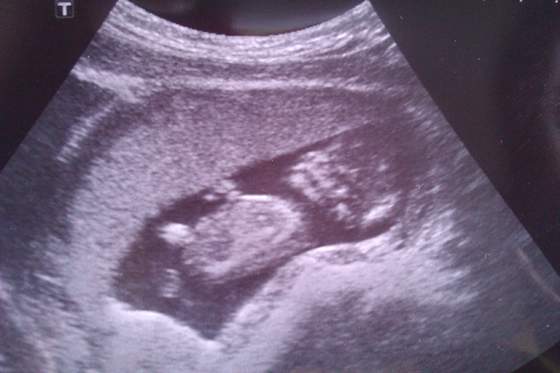

14 tydzien1.jpgDzidzia zdrowiutka i śliczna, ma już 63 mm. Ruchliwa mała mrówka :) Siusiaka narazie nie widać ale mam nadzieje że tam jest heh. Usg bałam się cholernie, jakoś przed każdym mam stresa jak na maturze czy wszystko jest ok, ale jak zobaczyłam tą buźkę to się poryczałam i poszłam do domku. Tak bardzo się cieszę że wszystko jest ok bo drugiej wpadki tfuuuu bym nie przeżyła